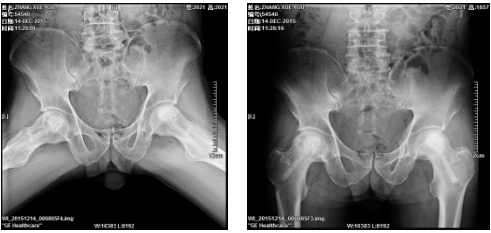

2、髋关节全髋、半髋置换手术、膝关节表面置换手术、关节融合手术。